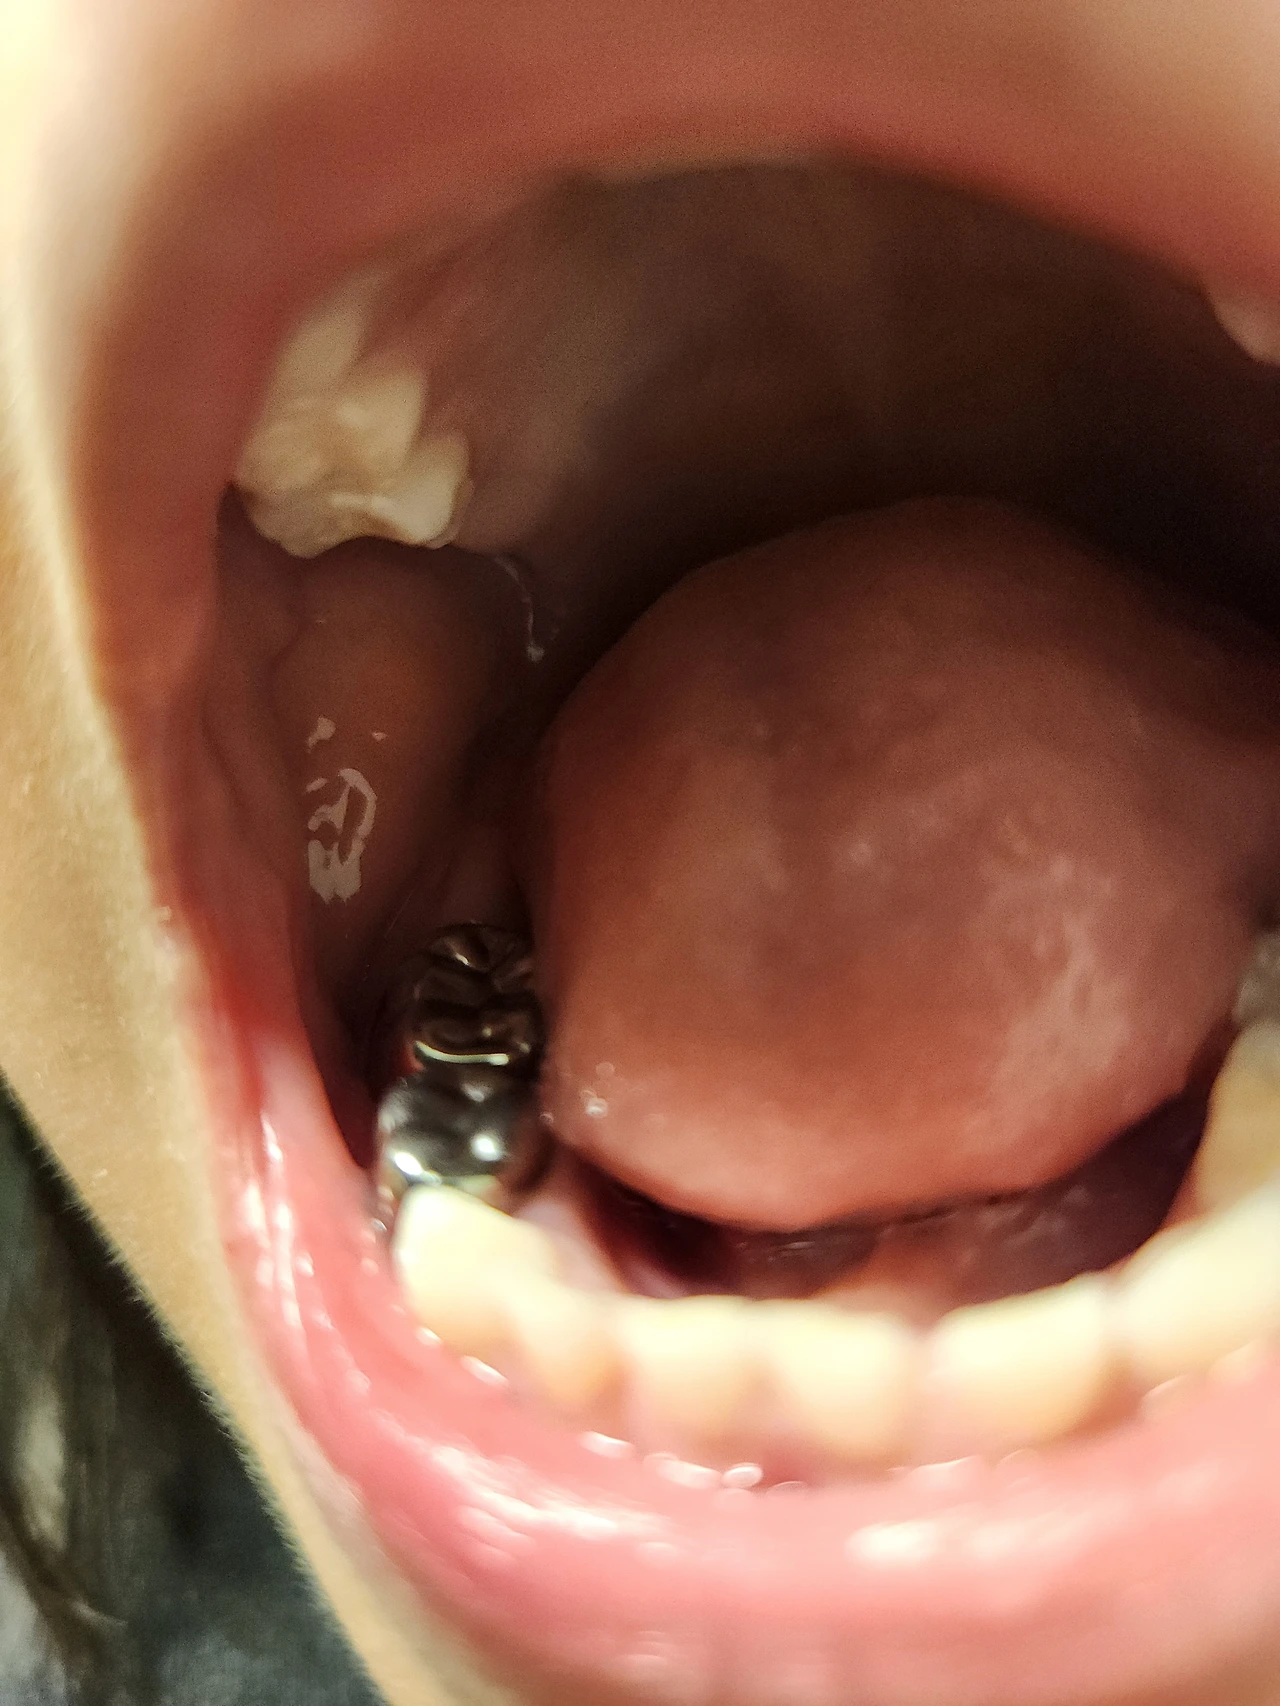

그 사이에 오피스에 가서 정기 미팅을 마치고 점심을 먹었다. 오후 2시에는 충치가 많은 다섯 살꼬마의 치과 검진이다. 다니던 치과에서 과잉치료를 한다고 생각하여 새로 생긴 한국인이 하는 치과로 옮겼다. 충치 치아가 더 있었으며, 필링과 비용이 같다면서 크라운 두 개를 넣었다. 그 사이 많이 자라서 힘들지 않게 치료를 마쳤다. 마취라는 것을 처음해봐서 그런지 그 느낌을 생생하게 들려줬다. 오후에는 아이가 잘 지내는지 원장님께서 전화도 해주셨다.치아 틈사이에 충치가 생겨서 치실사용은 흔한 일상이 되었다.티비를 보면서도 심심하면 하게 되었다.